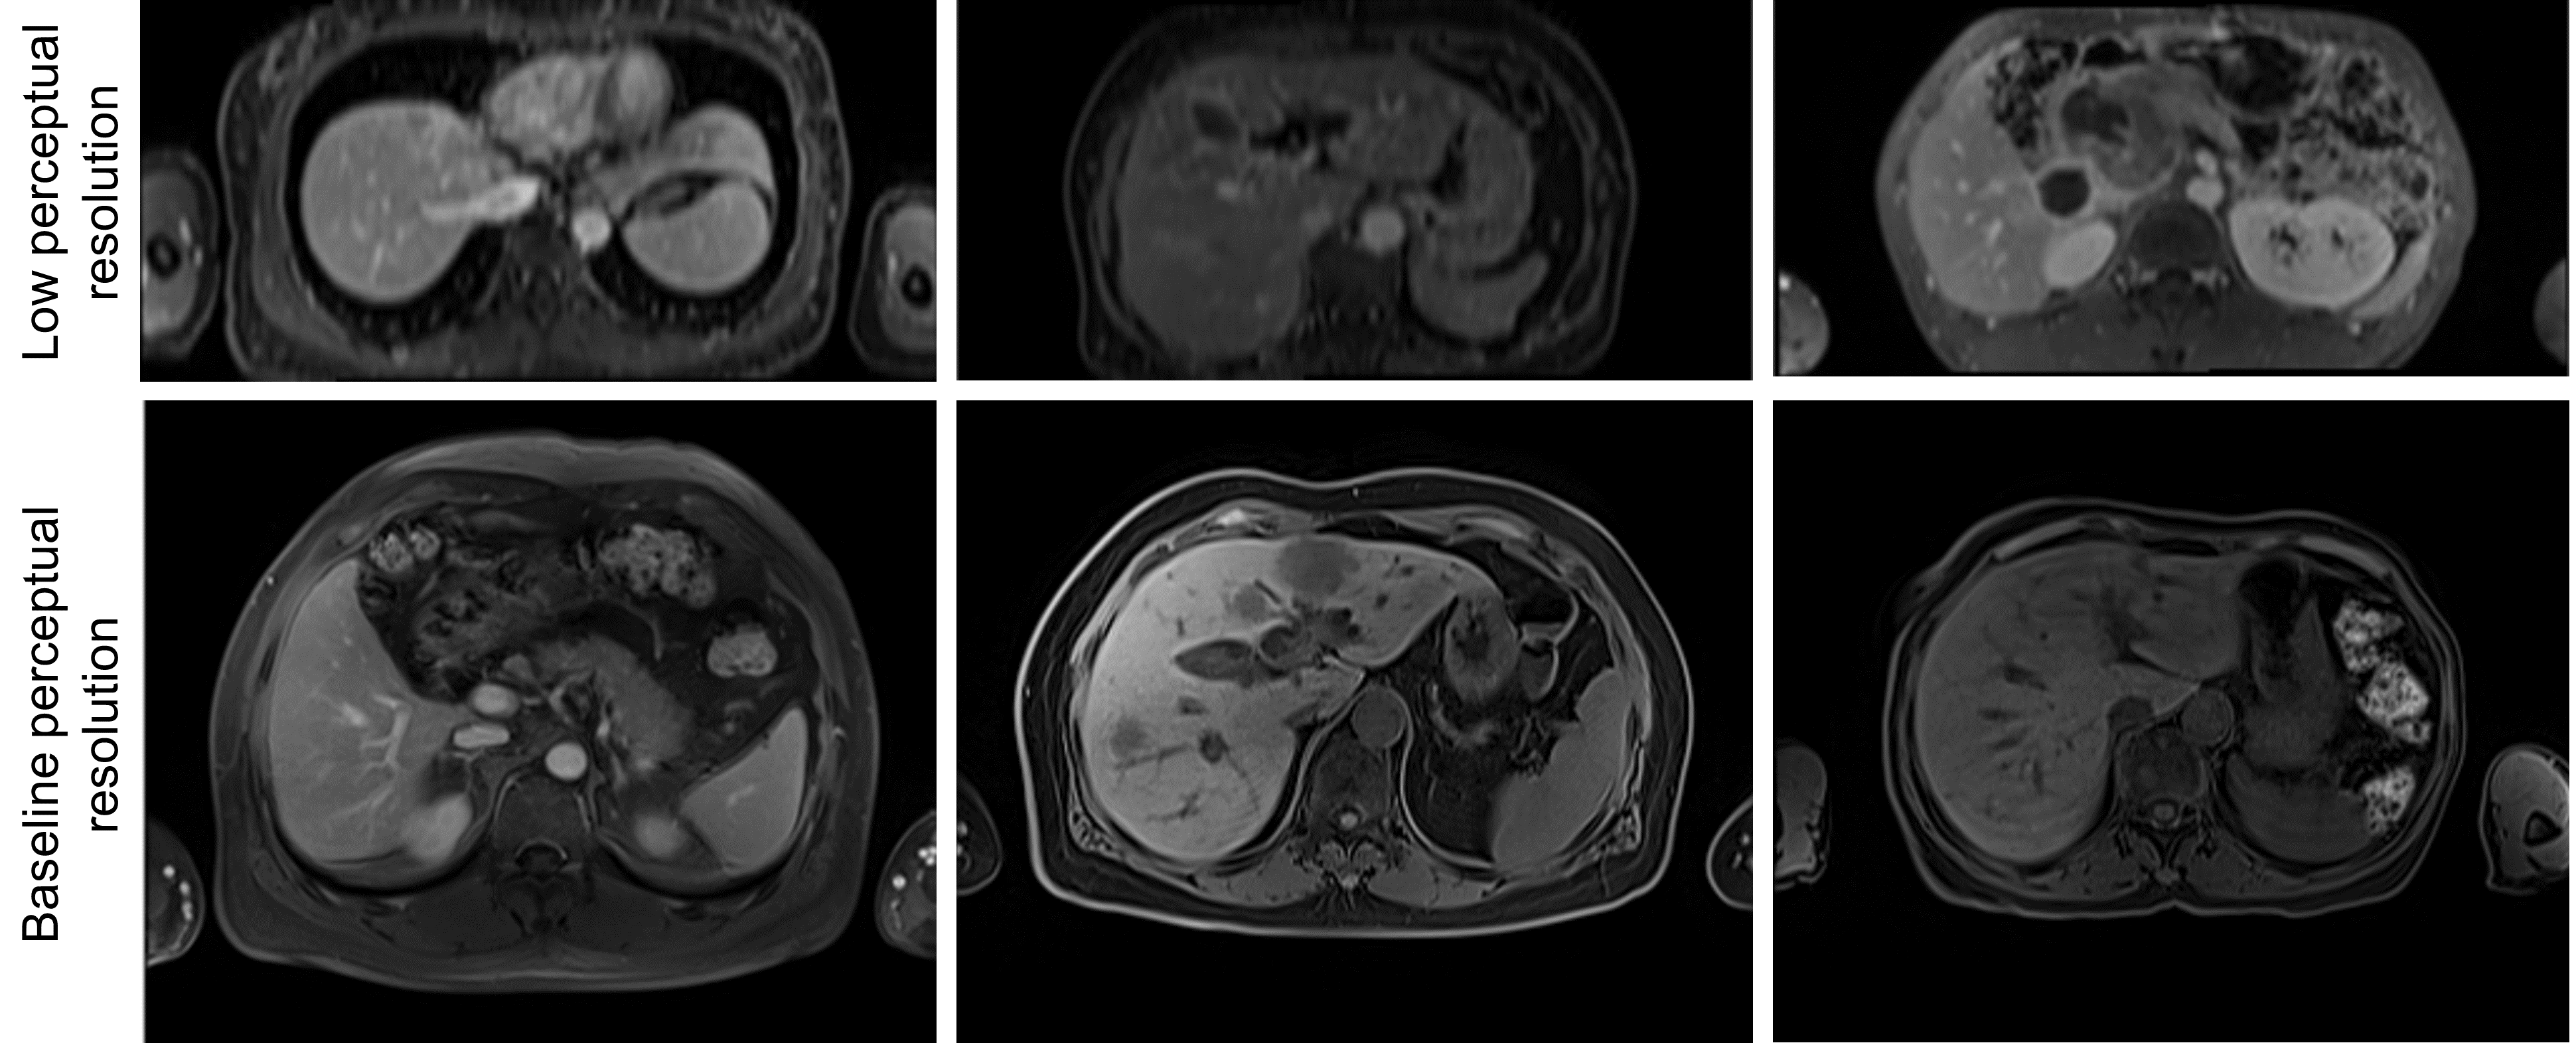

Figure 3 visualizes the 2D embeddings produced by PCA, t-SNE, and UMAP for the MRI UNETR. In addition, covariance ellipses generated by the training distribution are plotted, representing one and two standard deviations away from the mean training embedding. PCA mapped most ID test images within one standard deviation of the mean training embedding (the image not within the first deviation contained a motion artifact). On the other hand, most OOD test images were mapped outside of the first standard deviation. When test embeddings were visualized by their DSC, the three reduction techniques mapped the images with the lowest DSCs farthest from the mean training embedding. Moreover, all three techniques clustered training embeddings by source. The 26 images from the AMOS dataset mapped outside the second standard deviation by all techniques were deemed to be of low perceptual resolution by a physician. These were the only images from the AMOS dataset whose axial dimension was larger than the sagittal dimension. Sample images from both AMOS clusters are shown in Figure 5 in Appendix C.

Refer to caption

Figure 3: Visualization of 2D projections of MRI UNETR embeddings. (Top Row) PCA projections. (Middle Row) t-SNE projections. (Bottom Row) UMAP projections. (Left Column) Test projections split into ID and OOD by 95% DSC. (Middle Column) Test projections by DSC. (Right Column) Projections for the training data by source. The gray ellipses are the covariance ellipses (one and two standard deviations) for the training distribution.